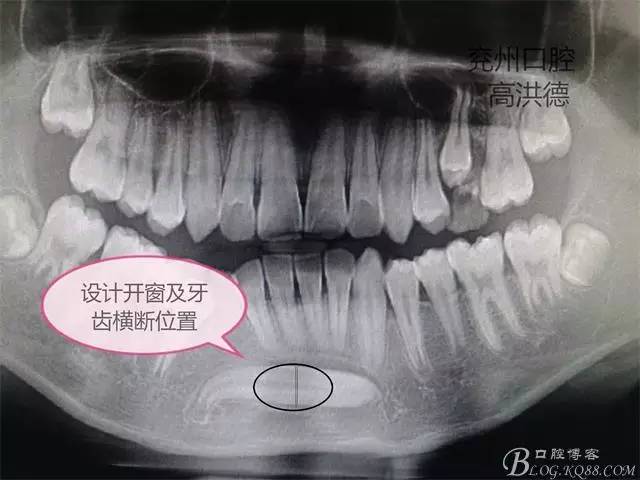

曲面斷層片顯示

手術設計;下頜前庭溝做約3CM的切口,分離粘骨膜,高速手機去骨,暴露牙齒中端,截斷牙齒分別取出,牙冠和牙根。